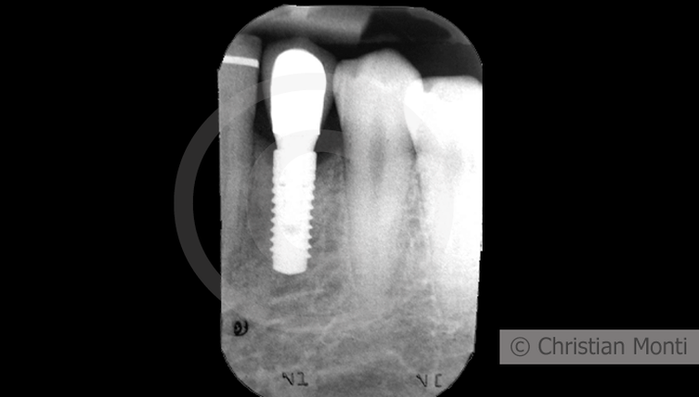

EDENTULIA SINGOLA

Impianto in sostituzione di un canino deciduo